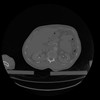

28 CUERPO,CE,Vol,2.0,CUERPO,,